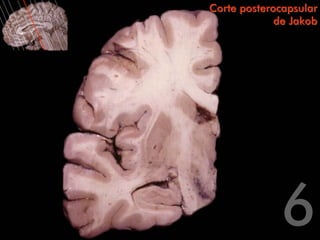

Circunvolución frontal superior   Corte posterocapsular

Surco frontal                                  de Jakob

superior

Circunvolución

frontal medial

Circunvolución frontal media

Surco del cíngulo

Surco frontal inferior                                                        Circunvolución del cíngulo

Circunvolución                                                                Tronco del cuerpo calloso

frontal inferior

Surco lateral

Circunvolución                                                            Centro oval del lóbulo

temporal superior                                                         frontal

Surco temporal

superior                                                              Lóbulo de la ínsula

Hipocampo

temporal media

temporal inferior

Brazo posterior de                        Corte posterocapsular

la cápsula interna                                     de Jakob

Cuerpo del núcleo caudado

Cápsula externa                                                         Tronco del cuerpo calloso

Cuerpo del ventrículo

Putamen                                                                 lateral

Septum pellucidum

Claustro

Cuerpo del fórnix

Cápsula

extrema                                                                 Tálamo

Globo pálido

Lámina medular

externa                                                                 Núcleo subtalámico

Tracto óptico

Cola del núcleo

caudado                                                                 Sustancia negra

Álveo del                                                        Fimbria

hipocampo                                         Asta temporal del ventrículo lateral

Asta de Ammon

Circunvolución frontal superior Corte posterocapsular Surco frontal de Jakob superior Circunvolución frontal medial Circunvolución frontal media Surco del cíngulo Surco frontal inferior Circunvolución del cíngulo Circunvolución Tronco del cuerpo calloso frontal inferior Surco lateral Circunvolución Centro oval del lóbulo temporal superior frontal Surco temporal superior Lóbulo de la ínsula Hipocampo Circunvolución temporal media Circunvolución temporal inferior

Brazo posterior de Corte posterocapsular la cápsula interna de Jakob Cuerpo del núcleo caudado Cápsula externa Tronco del cuerpo calloso Cuerpo del ventrículo Putamen lateral Septum pellucidum Claustro Cuerpo del fórnix Cápsula extrema Tálamo Globo pálido Lámina medular externa Núcleo subtalámico Tracto óptico Cola del núcleo caudado Sustancia negra Álveo del Fimbria hipocampo Asta temporal del ventrículo lateral Asta de Ammon